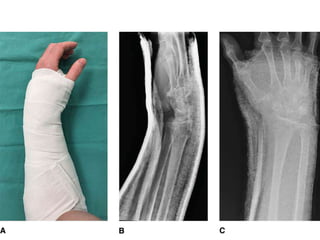

Incruento

• Fracturas no desplazadas se pueden tratar con reducción cerrada e

inmovilización.

• Yeso en 20º de flexión palmar y desviación cubital.

• Debe evitarse la flexión extrema de la muñeca. (Cotton-Loder)

• Duración de la fijación de yeso 6 semanas

Tiempos en tratamiento incruento

• Valva braquipalmar posterior 4 dias

• Yeso cerrado braquipalmar 4 semanas

• Liberacion codo

• Yeso cerrado antebraquipalmar 2 semanas

• Evaluación semanal por varias semanas

EN PACIENTES ANCIANOS

COLOCAR ALGODONADO EN

SITIO DELA MANIOBRA PARA

EL CUIDADO DE LA PIEL

Minimización dela rigidez en la mano